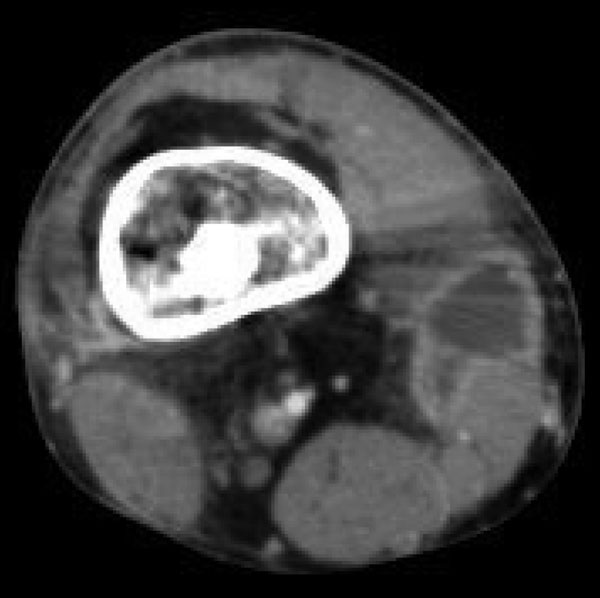

Ewing Sarcoma

Ewing sarcoma is characterized by the malignant proliferation of poorly differentiated cells.

Ewing sarcoma typically affects male children under the age of 15-years-old.

Ewing sarcoma generally manifests in the diaphysis of the long bones.

Radiology of Ewing sarcoma classically has an “onion-skin” appearance on X-ray.

Diagnosis of Ewing sarcoma is made by biopsy that reveals small, round, blue cells that look similar to lymphocytes.

Malignant cells of Ewing sarcoma stain positive for CD99.

Genetic tests for Ewing sarcoma tend to show EWSR translocations, such as EWSR-FLI1.

Ewing sarcoma is treated by chemotherapy.